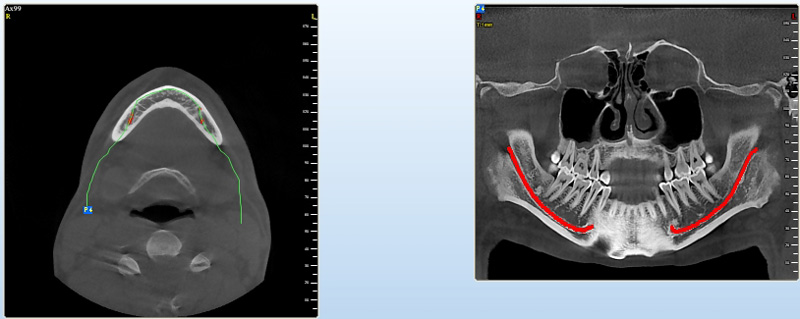

Jedná se o nejnovějším přístroj ze skupiny dentálních hybridních CBCT (3D) + 2D (pan i ceph) systémů. Přístroj umožňuje na základě jediného snímkování vytvořit všechny typy RTG zobrazení, které jsou pro lékaře potřebné.

Používaná technologii tzv. „kuželového paprsku“ a speciální senzory pro minimální zátěž při snímkování pacienta

(o více jak 80% nižší dávka proti klasickému CT).

Pomocí tohoto přístroje je možné zjisti skutečnou situaci v čelistních kostech pacienta tedy množství kosti - můžeme změřit skutečnou šířku i výšku kosti, i kvalitu kosti (hustotu) v místě uvažované implantace. 3D (tříprostorové) zobrazení umožňuje

zvýšit prostorovou představu operatéra ještě před vlastní operací a zároveň pacientovi lépe objasnit a ukázat oblast plánovaného zavedení implantátu.

Pacient „neumí číst“ RTG snímky, ale díky 3D zobrazení vidí „svoji skutečnou čelist“ – např. jak je nízká či úzká, vidí průběh nervu nebo velikost čelistní dutiny, což mu umožní i pochopení nutnosti v některých případech provést pomocné zákroky

ještě před vlastním zavedením implantátu (více - Augmentace - kostní štěp, sinus lift, kostní granulát...).

Pomocí počítačových programů – NewTom Implant Planning a coDiagnostiX si lékař sám provádí veškerá potřebná zobrazení a měření.

Vyšetření pomocí tohoto přístroje a získaná data používáme

pro každou implantaci, dále ve stomatochirurgii (zlomeniny čelistí, zuby moudrosti, cysty, onemocnění čelistního kloubu), ortodoncii (retinované zuby, nadpočetné zuby), parodontologii atd.